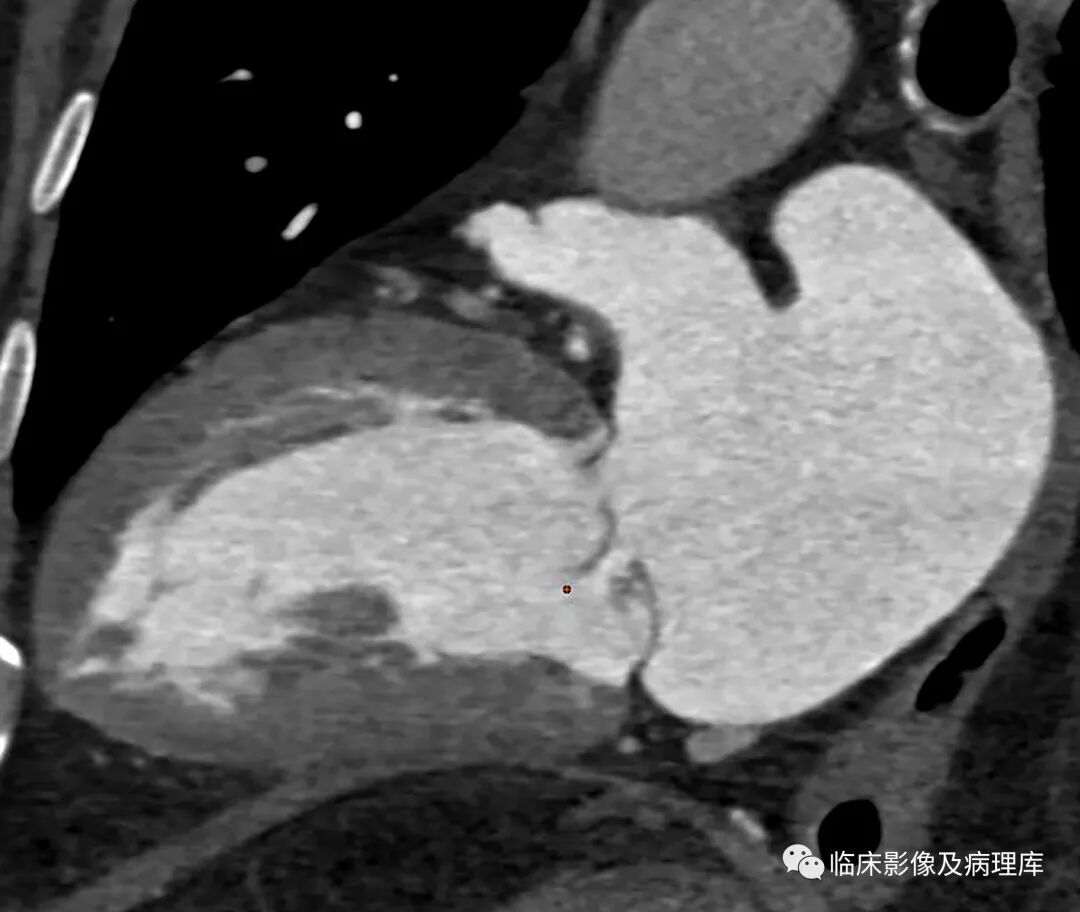

二尖瓣脱垂CT表现

上图分别为轴位及心室长轴位,显示收缩期二尖瓣后叶突向左心房内